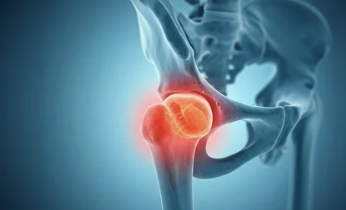

2️⃣ 대퇴골두 무혈성 괴사

- 설명: 대퇴골의 머리 부분에 혈류가 차단되어 뼈가 괴사하는 질환

- 원인: 과음, 스테로이드 남용, 외상 등

- 주요 증상:

- 갑작스러운 사타구니 통증

- 앉았다 일어날 때 유독 아픔

- 양반다리 어려움